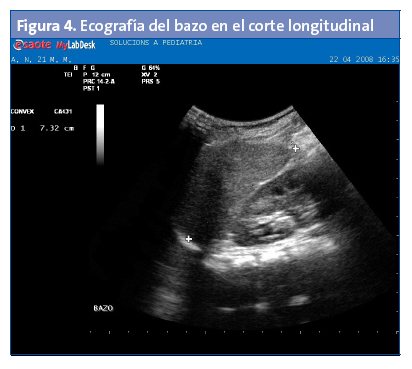

El bazo tiene una ecoestructura fina, homogénea, el contorno es liso y es ligeramente más hipoecogénico que el hígado (Fig. 4). Hacia abajo está el riñón izquierdo.